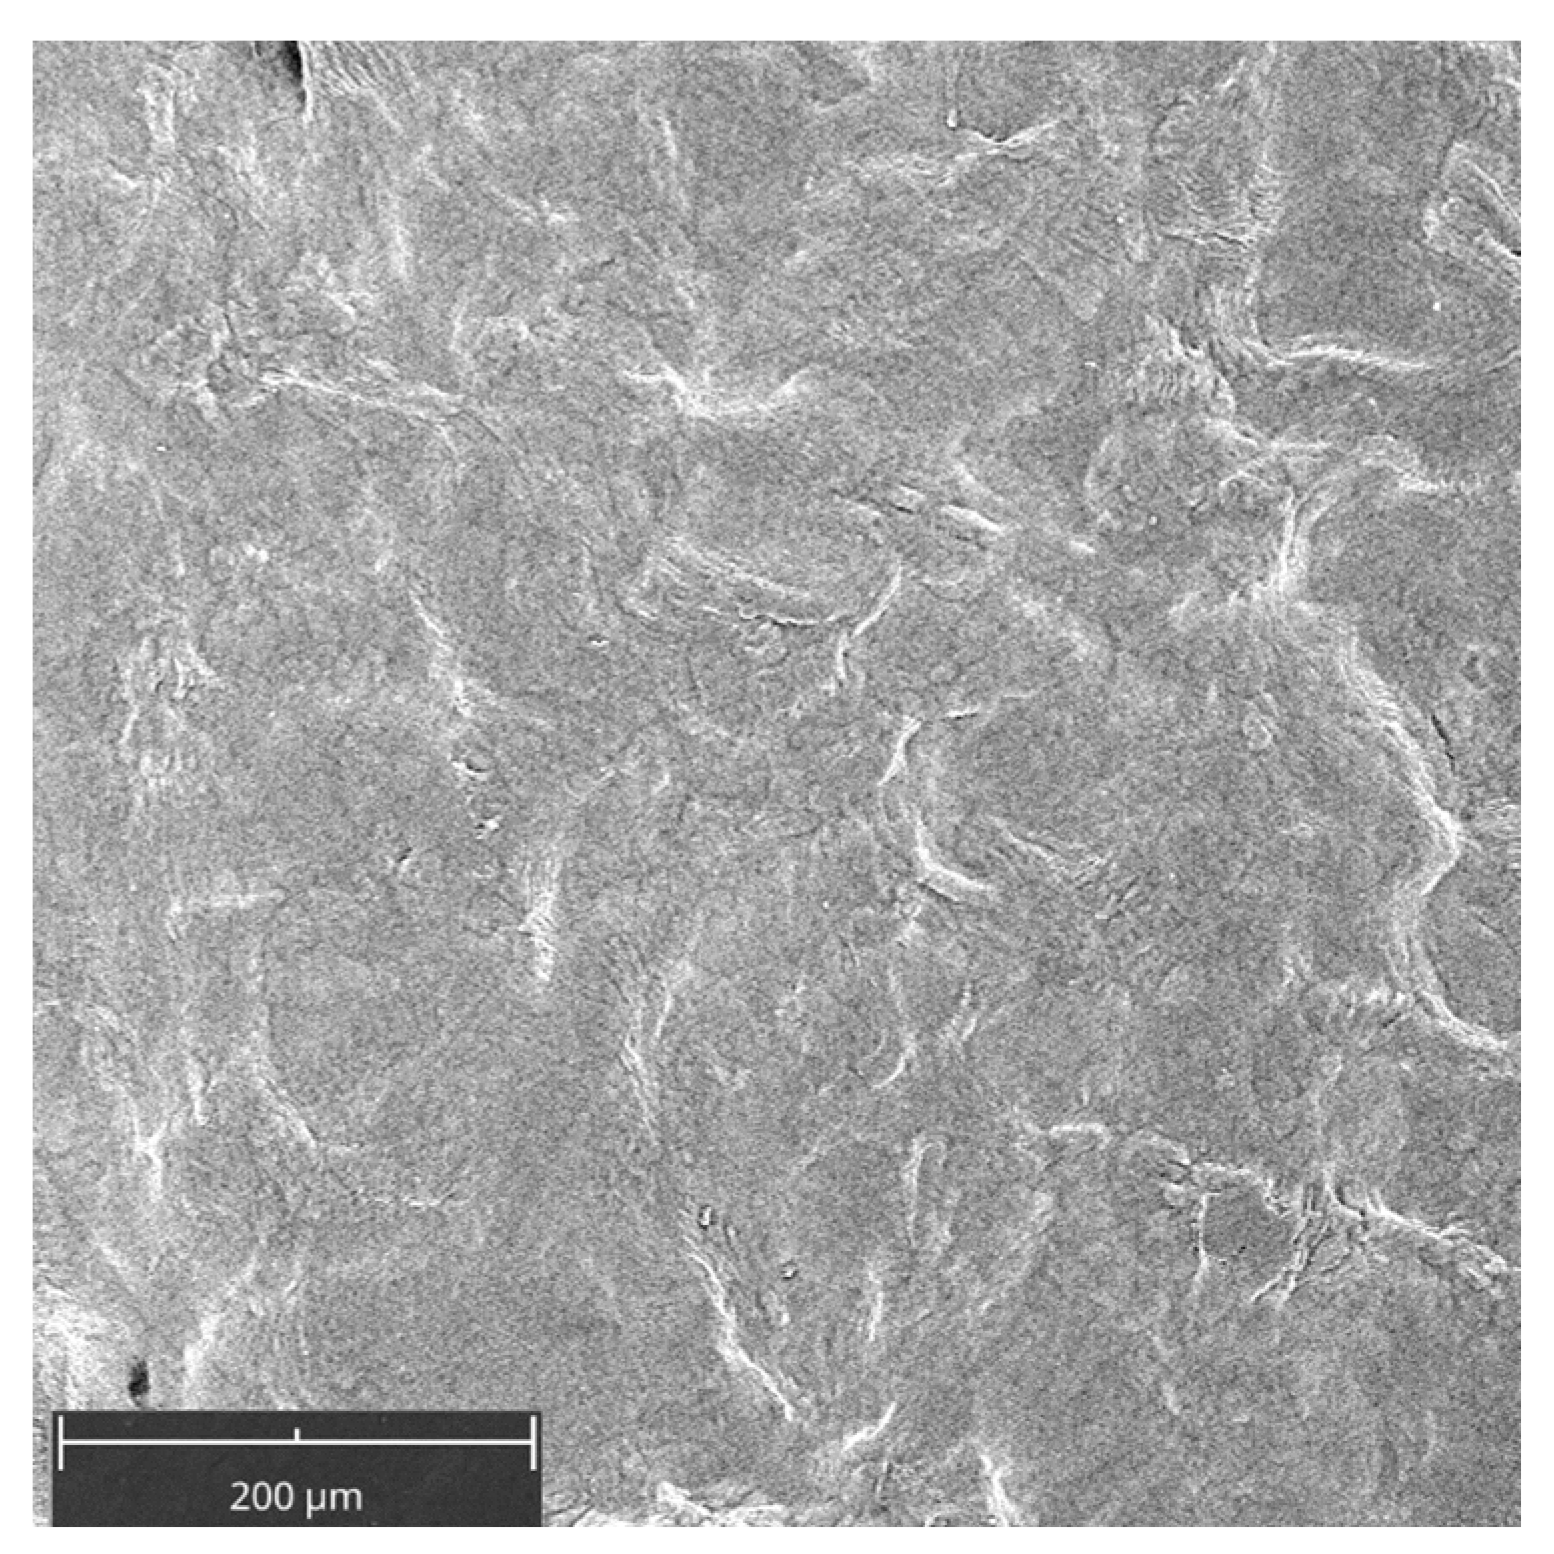

2.1. Cell Attachment on the PADMM after ALAD-PDT

Figure 1 shows the membrane without cells. Its surface appeared smoothed. Cell adhesion was evaluated by SEM at 3, 7, and 14 days (Figure 2 and Figure 3). At 3 days, HGFs colonized the surface of the matrix, especially after the ALAD-PDT protocol, as observed in the different magnifications (Figure 2). At 1000×, the presence of elongated and spindle-shaped with cytoplasmic extensions and lamellipodia were recognizable. Confluence was reached after 7 days; at 14 days, the cells covered the matrix entirely. At 14 days, the morphology of cells was not notable because of the high density of cells.

Figure 1. Scanning electron microscopy (SEM) images of the membrane (PADMM) without cells. Magnification 390×.